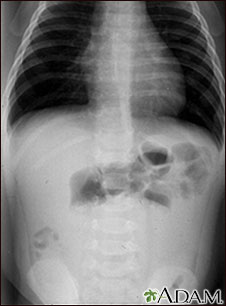

Exams and Tests

During a physical exam, the health care provider may find bloating, tenderness, or hernias in the abdomen.

Tests that show obstruction include:

- Abdominal CT scan

- Abdominal x-ray

- Barium enema

- Upper GI and small bowel series

In a newborn, paralytic ileus that destroys the bowel wall (necrotizing enterocolitis) is a life-threatening condition. It may lead to blood and lung infections.